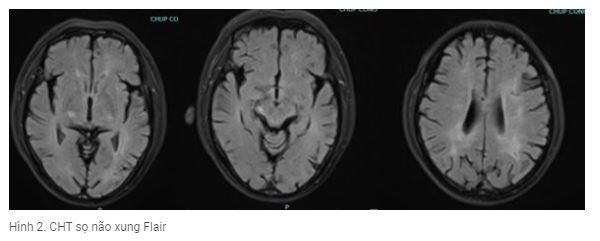

Với bệnh sử từ trước kết hợp với lâm sàng khởi phát bởi co giật và rối loạn tâm thần và bất thường trong dịch não tủy, các bác sĩ trong trung tâm đột quỵ đã hội chẩn và nghĩ nhiều đến viêm não tự miễn và chỉ định xét nghiệm một số xét nghiệm viêm não tự miễn (làm tại bệnh viện Nhi trung ương) và kết quả mẫu huyết thanh của bệnh nhân dương tính với kháng thể kháng LGI1 (Leucine-rich glioma-inactivated 1) (hình 3). Kháng thể LG1 là một trong 6 loại tự kháng thể phổ biến trong bệnh viêm não tự miễn đang được xét nghiệm chẩn đoán tại Việt Nam.

Kết quả xét nghiệm viêm não tự miễn |